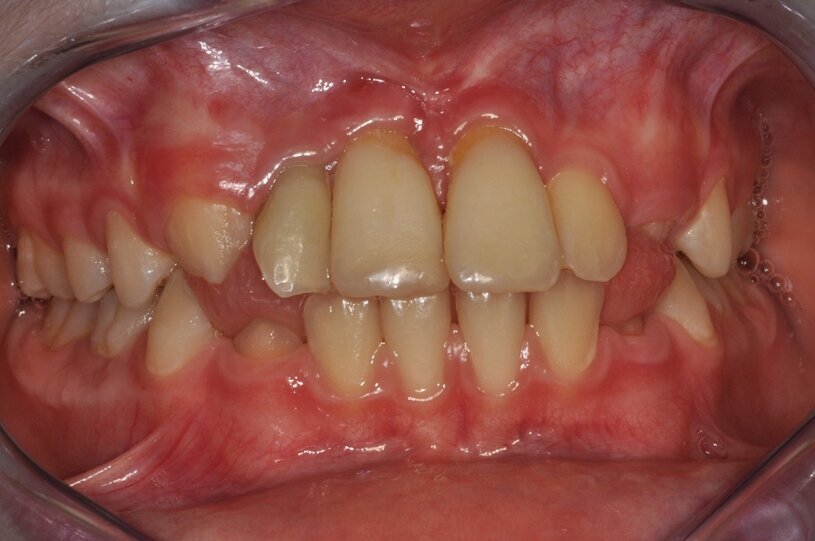

W znieczuleniu nasiękowym 1 amp. 4% Ubistesin Forte nacięto i odwarstwiono płat trapezowy śluzówkowo-okostnowy w okolicy 13 do 23. Zęby 11 i 21 usunięto w całości (Ryc. 3 i 4). Wykonano ablację kości laserem Er:YAG (LightWalker® Fotona®), (2 W, 10 Hz, 200 mJ, QSP) usuwając ziarninę zapalną, a następnie laserem Nd:YAG (LightWalker®, Fotona®), (1,5 W, 10 Hz, MSP) przeprowadzono redukcję bakterii (Fotona®).

Ryc. 4¬_Stan miejscowy po ekstrakcji i ablacji kości.